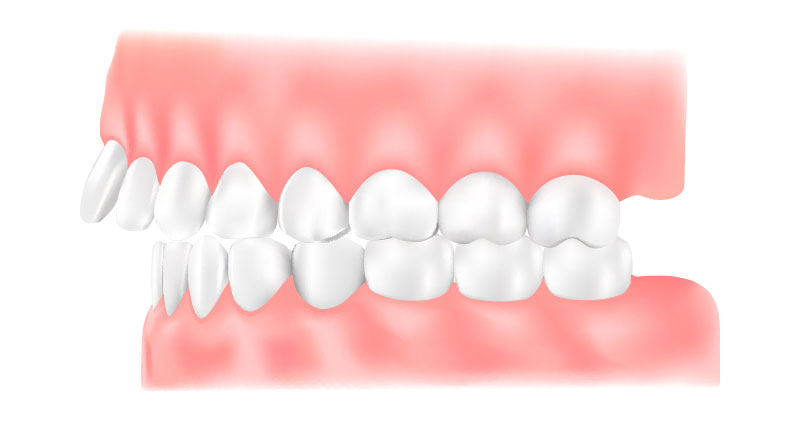

矯正歯科は、歯並びや噛み合わせを整える治療です。見た目の改善に加え、噛みやすさや磨きやすさが向上することで、むし歯や歯周病の予防にもつながります。また、噛み合わせが原因で歯周病が進行したり、歯が割れる、補綴物が壊れるといったトラブルが起きている場合には、その改善策として矯正治療を提案することもあります。

矯正歯科